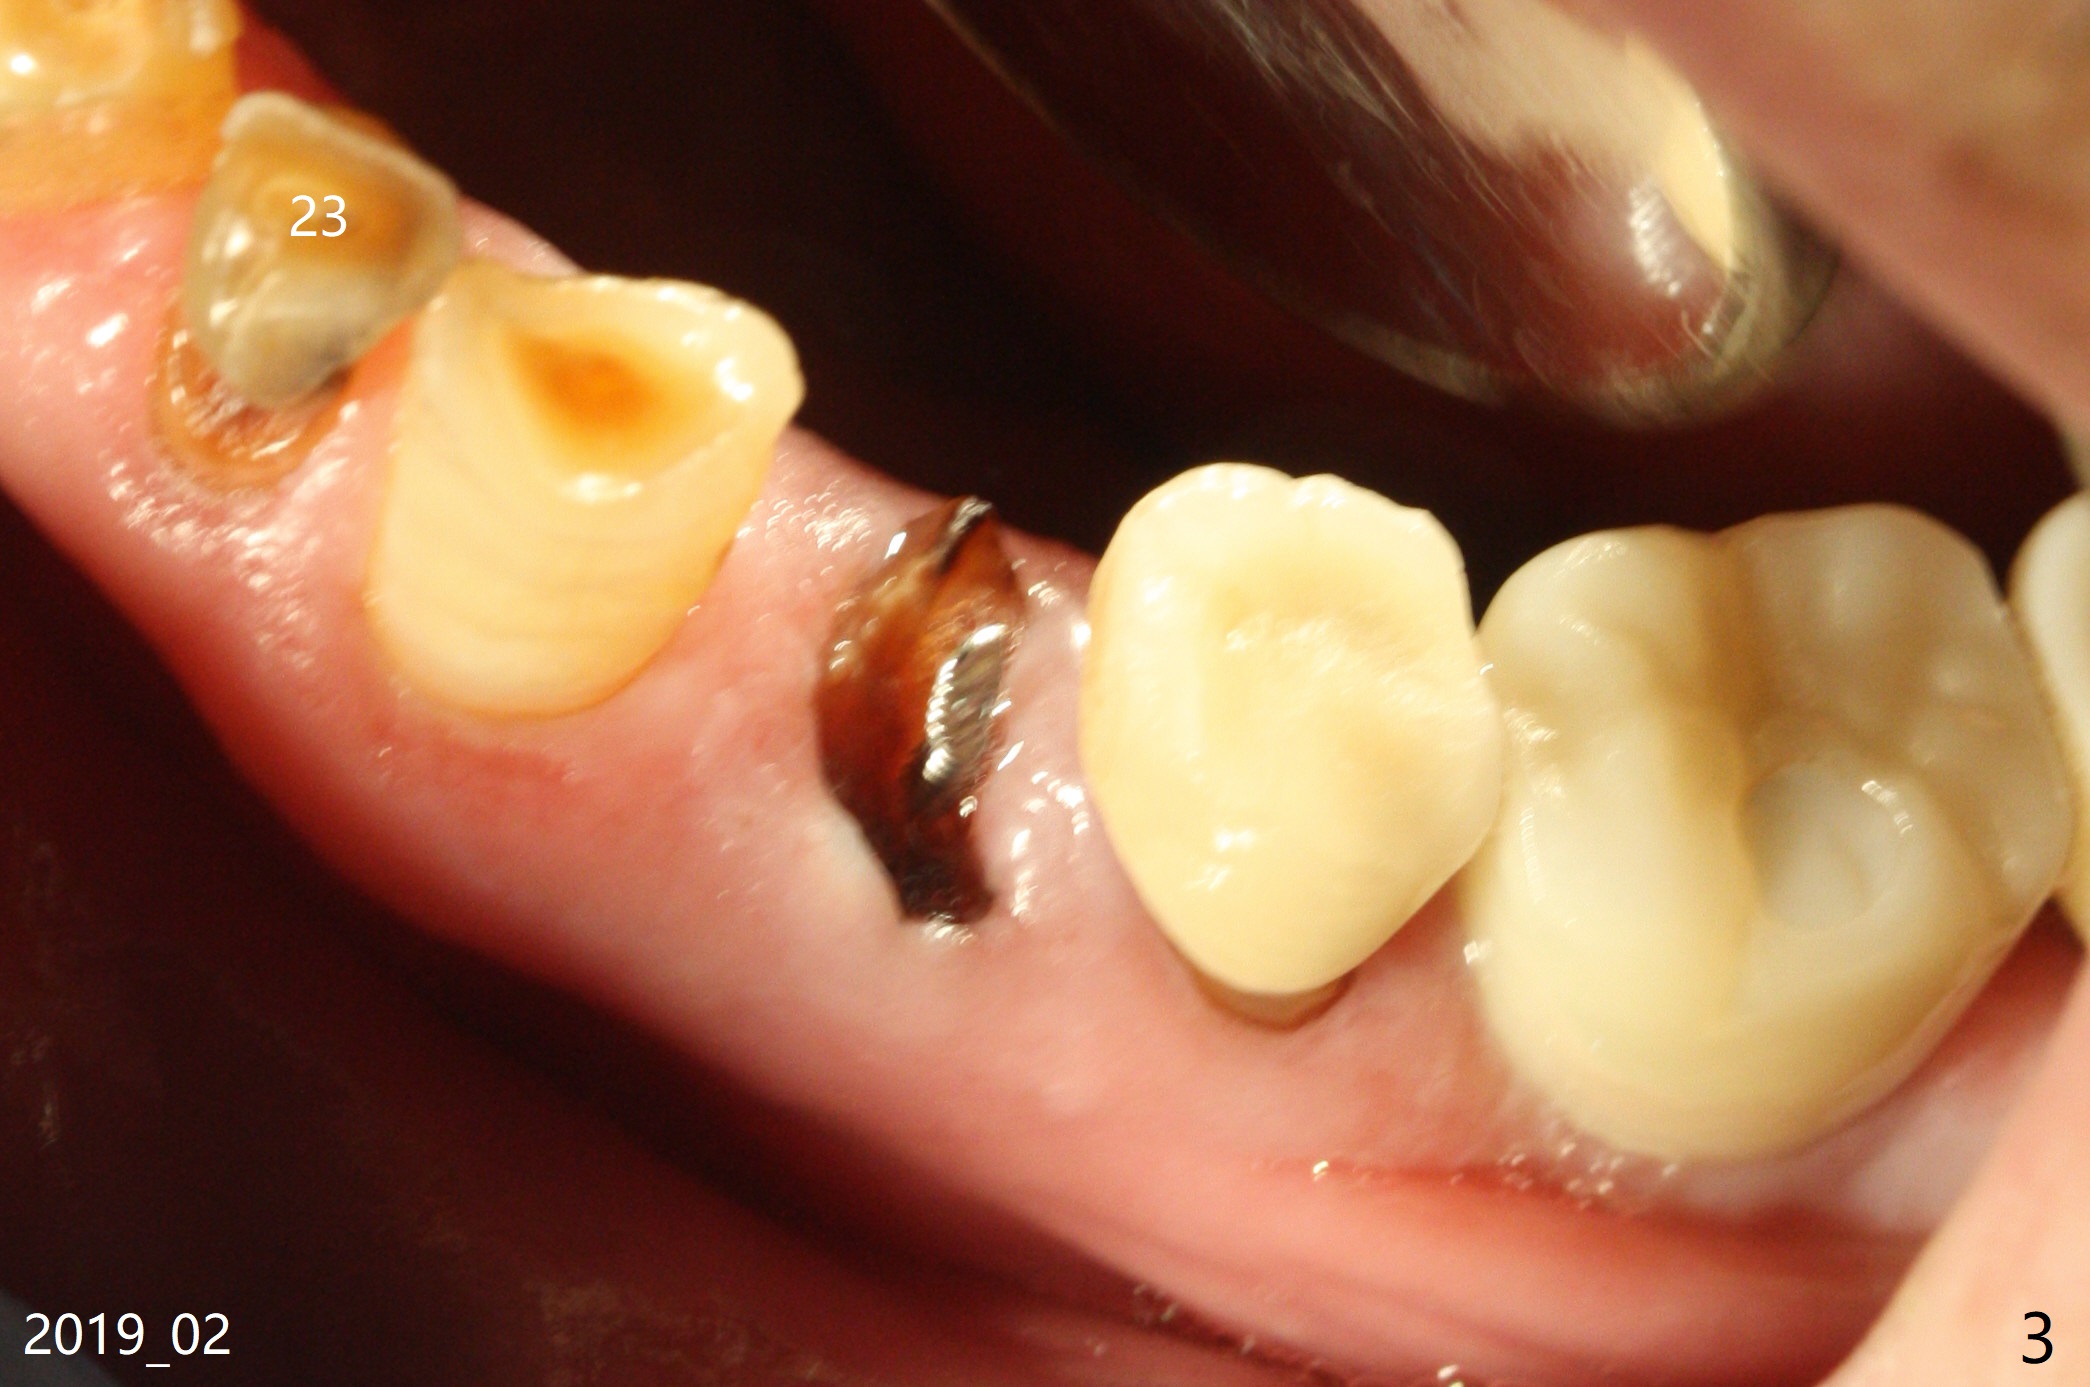

A 88-year-old man breaks the tooth #21 after RCT and post (Fig.1-3). Place a long SM implant for early final restoration, since he is a bruxer. The diameter of the implant will be 3.8-4.5 mm (Fig.2). Place the implant in the middle of the oval socket. Prepare endo ice for #23 before composite (Fig.3).